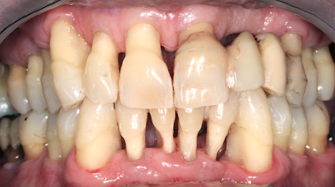

Nella foto sopra pubblicata sono rappresentati alcuni casi di malattie parodontali gravi che, con i trattamenti adeguati si è riusciti a stabilizzare nel tempo, arrestando la perdita di osso intorno ai denti e mantenendo buona parte dei denti presenti a inizio trattamento. Sono frutto di un corretto trattamento, una eccellente igiene orale del paziente, ed una frequenza elevata delle visite di controllo (trimestrali). Questi casi dimostrano l'efficacia nel tempo di un trattamento corretto anche in caso di parodontopatie gravissime.

Paziente con gravissima malattia parodontale stabilizzzata. A distanza di 11 anni i livelli ossei e gengivali si mantengono pressochè immutati. Merito del trattamento, dei controlli trimestrali e di una scrupolosissima igiene domiciliare.